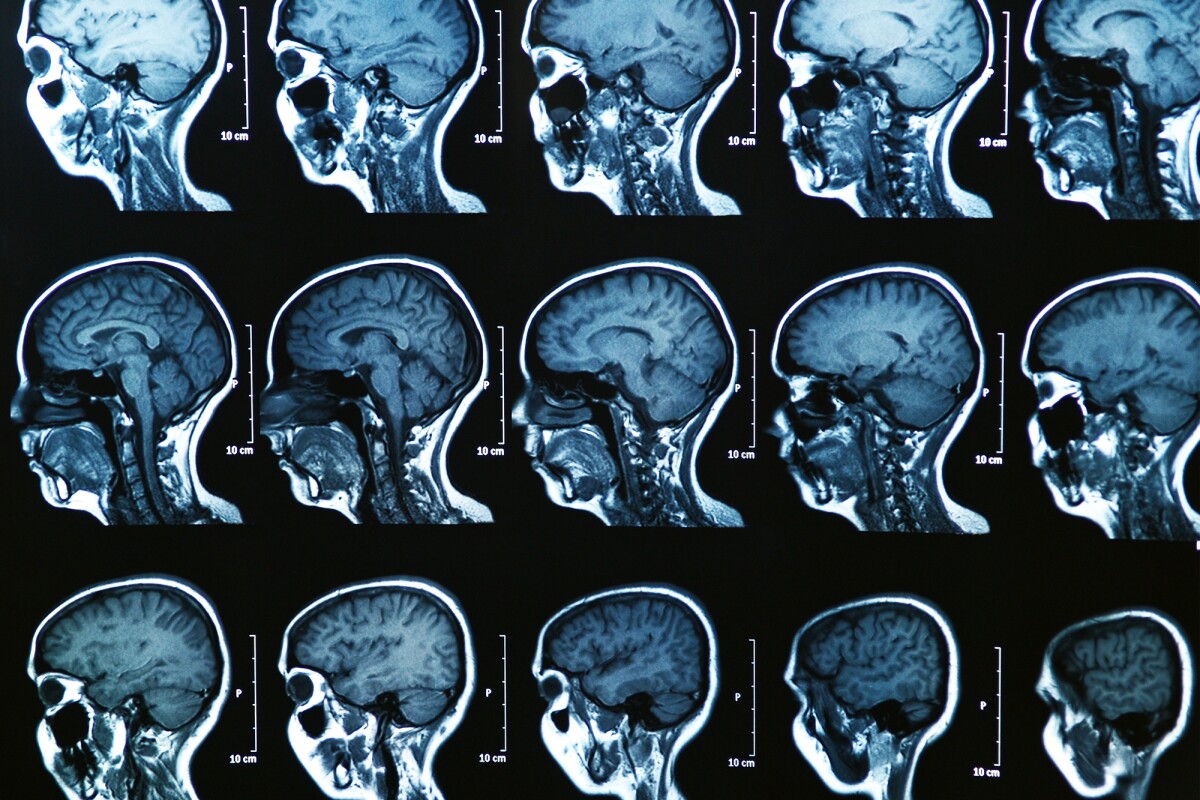

Спустя 11 месяцев близкие артиста вновь ошарашили фанатов «Крепкого орешка» печальными новостями. Семья сообщила, что Брюсу диагностировали лобно-височную деменцию, отметив, что недуг прогнозирует.

Порой все понимают сути деменции. Дело в том, что человек с каждым днем медленно «утекает» из жизни. Больше не может контролировать собственные потребности, нормально и комфортно коммуницировать с людьми, объяснять и просить то, что ему необходимо. Пациент теряет рабочие и бытовые навыки, постепенно перестает помнить окружающих и даже самого себя.

За последние десять лет недуг начал проявляться намного чаще, хотя заболевание считалось очень редким. Теперь же лобно-височная деменция встречается в относительно молодом возрасте.

Эксперты предупреждают, что актер со временем совсем перестанет узнавать родственников, говорить, понимать речь и самостоятельно двигаться.

«Состояние актера перейдет в вегетативное, которое может длиться довольно долго, время нахождения в нем зависит от ухода и качества медицинской помощи. В данном случае дать точный прогноз довольно сложно, потому что есть высокий риск осложнений, инфекций, продолжительность жизни зависит от получаемой медицинской помощи.

Но даже если человек получает ее в максимальном объеме, нельзя исключать, что возможен высокий риск осложнений от сопутствующих заболеваний», — объяснил в интервью с «Вечерней Москвой» врач-психиатр Алексей Вилков.

По словам врача, прожить в таком состоянии возможно от нескольких месяцев до нескольких лет, не более.